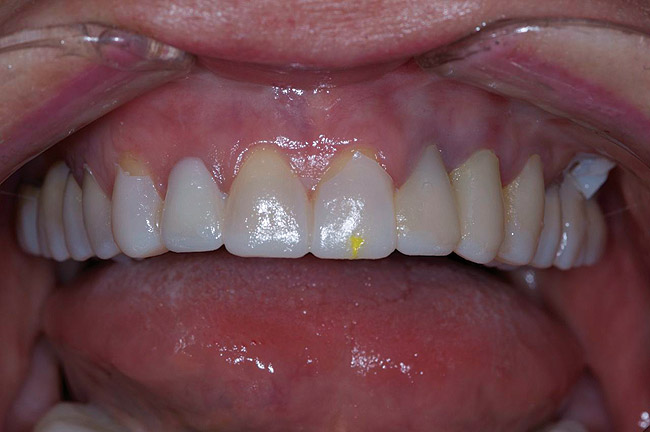

Figure 3  Preoperative view. Note the worn incisal edges and end-on-end occlusal relationship requiring an increase in OVD to restore.

Figure 3

Figure 4  Interocclusal registration made at the approximate OVD for rehabilitation.

Figure 4

Figure 5  Accurate casts mounted at arbitrary OVD.

Figure 5

The registration of the transverse hinge axis and transfer with a facebow simply serves to locate the maxillary cast on the articulator. An accurate registration of centric relation allows the laboratory to mount the mandibular cast in a repeatable position for the purposes of reconstruction.18 Commonly, interocclusal records provided to the laboratory are with teeth in contact or the laboratory is asked to hand-articulate without the benefit of a bite registration. Besides a lack of repeatability, casts mounted in contact must be separated to a working vertical dimension. Because the earbow/facebow mounting is an arbitrary positioning of the maxilla, the casts will routinely not be on the same arc of closure as found intraorally. This means that as the casts are separated there is the possibility of a significant anterior–posterior shift.19 The error compounds the farther from the true hinge axis the facebow was fabricated and the greater the casts are opened on the arbitrary arc. Because of this magnifying error, Gracis suggests that interocclusal records should be fabricated at the vertical dimension that they will be rehabilitated.19 Dentists should visualize the ideal incisal edge position of the maxillary incisors and their ability to couple at the proposed vertical. Evaluating the patient’s central incisor display in repose and full smile arrives at this position.17 The author then uses a leaf gauge to separate the anterior teeth enough to accommodate the additional length (Figure 3 through Figure 5). The leaf gauge has the additional benefit of allowing the interocclusal registration to be fabricated with a seated condyle. This is obviously an arbitrary choice. The laboratory technician will alter the position during the diagnostic wax-up. Due to the fact that the registration is fabricated in an open relationship, the amount of modification in the OVD on the articulator will be significantly less. This will minimize the error found in wax-ups fabricated from a closed interocclusal record.